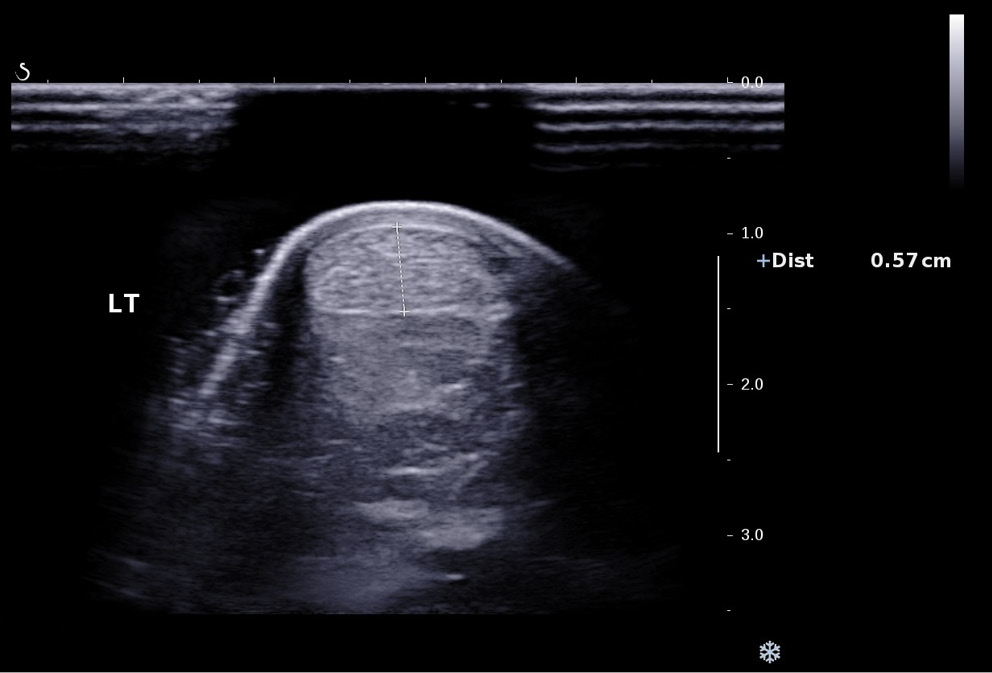

B-mode grayscale sonography in the longitudinal and axial planes was performed. Conditions of the area around the left and right Achilles tendons were evaluated. The irregular thickening around the Achilles tendon, heterogeneity of echotexture of the tendon and calcification of the calcaneal attachment were considered incidences of tendinopathy.3 Then, power Doppler of the whole tendons was performed, and the thickness of the left and right Achilles tendons was evaluated. Achilles tendinopathy was considered if tendons were more than 0.60 cm thick.19 The representative image for power Doppler of the tendon is presented in Figure 1.